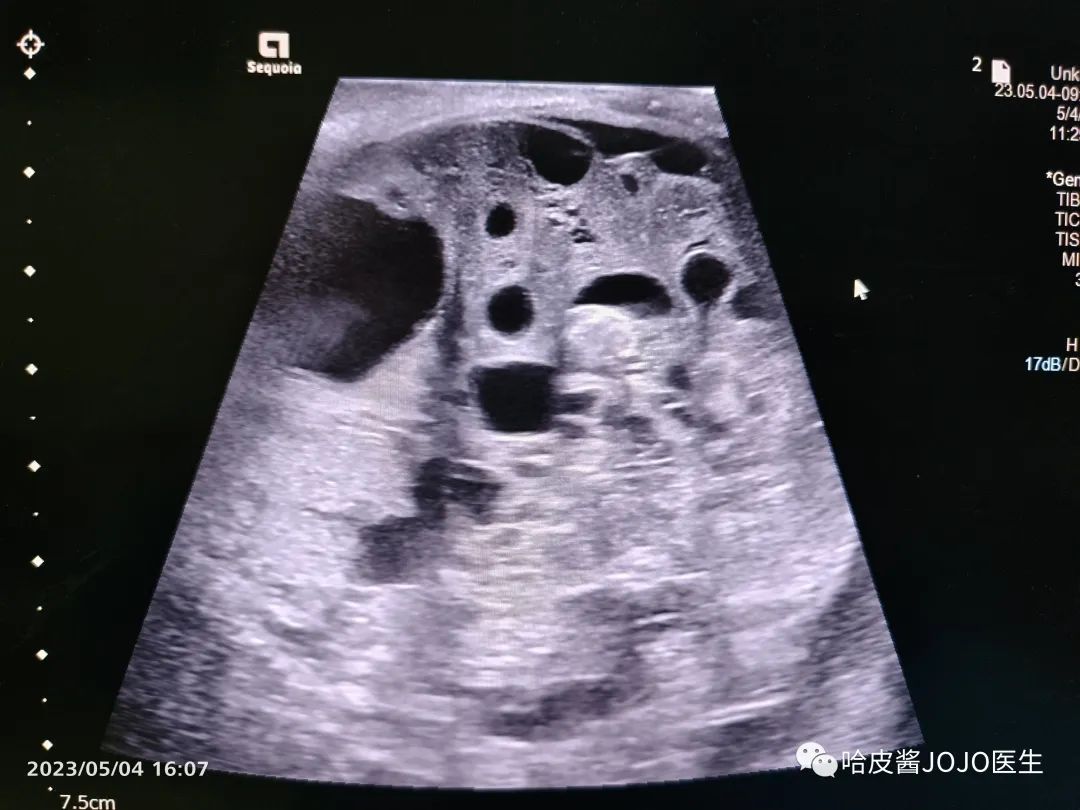

以下是超声图像↓

骶尾部囊实性包块,血供不是很丰富